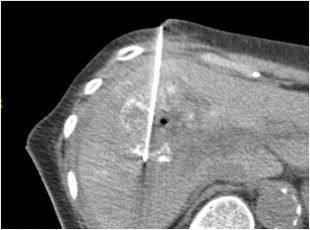

当院では肝臓ラジオ波治療および腹腔鏡手術を積極的に行っています。

RFA